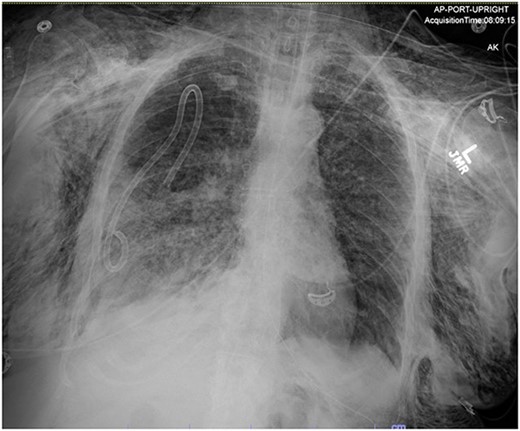

In the operating room (OR), the patient underwent intubation for TBNA using the Monarch® robotic bronchoscopy platform. Nine needle aspirations were obtained from the third-order RLL bronchi with each aliquot subjected to rapid on-site examination. While awaiting results, the patient developed retching, hemoptysis, bronchial bleeding from the superior segment of the RLL lobe and hypotension. The bleeding was managed with ice-cold saline and epinephrine. The patient required aggressive resuscitation with crystalloid, blood products and vasopressor therapy. She was transferred to the ICU where she remained intubated for ongoing resuscitation. In the ICU, the patient developed recurrent hypotension. Chest X-ray (CXR) revealed a right-sided pneumothorax (Fig. 1) that was treated with a small-bore pigtail chest tube and resulted in immediate improvement of her tension physiology. The pneumothorax resolved on repeat chest film while the patient remained intubated and sedated (Fig. 2).